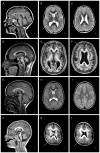

Lissencephaly ("smooth brain," LIS) is a malformation of cortical development associated with deficient neuronal migration and abnormal formation of cerebral convolutions or gyri. The LIS spectrum includes agyria, pachygyria, and subcortical band heterotopia. Our first classification of LIS and subcortical band heterotopia (SBH) was developed to distinguish between the first two genetic causes of LIS-LIS1 (PAFAH1B1) and DCX. However, progress in molecular genetics has led to identification of 19 LIS-associated genes, leaving the existing classification system insufficient to distinguish the increasingly diverse patterns of LIS. To address this challenge, we reviewed clinical, imaging and molecular data on 188 patients with LIS-SBH ascertained during the last 5 years, and reviewed selected archival data on another ∼1,400 patients. Using these data plus published reports, we constructed a new imaging based classification system with 21 recognizable patterns that reliably predict the most likely causative genes. These patterns do not correlate consistently with the clinical outcome, leading us to also develop a new scale useful for predicting clinical severity and outcome. Taken together, our work provides new tools that should prove useful for clinical management and genetic counselling of patients with LIS-SBH (imaging and severity based classifications), and guidance for prioritizing and interpreting genetic testing results (imaging based- classification).